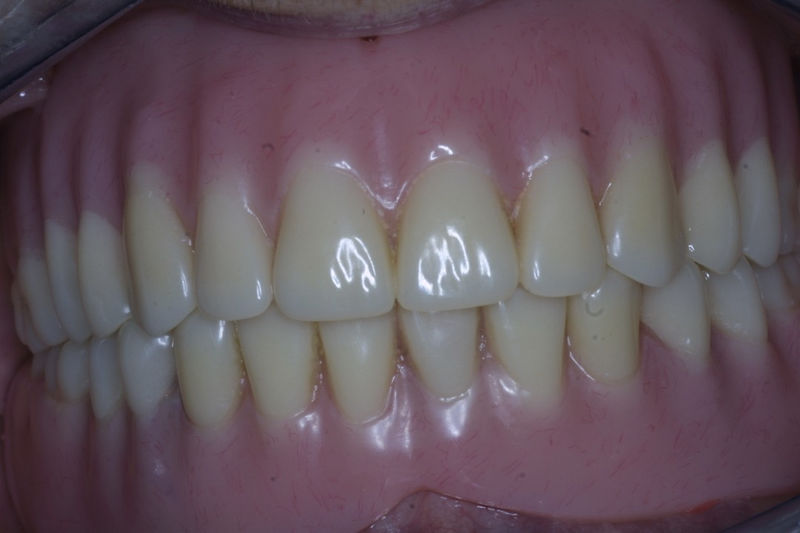

Amplia gama de tratamientos para mejorar la apariencia de la sonrisa, corrigiendo el color, la forma, el tamaño, la alineación y la posición de los dientes. Los procedimientos más comunes y solicitados incluyen el blanqueamiento dental, las carillas y coronas, así como las resinas.

Nuestro objetivo es mejorar la salud, la función y la estética bucal mediante planes de tratamiento completos, diseñados a la medida de las necesidades de cada persona.

Implante fracasado, extracción, carillas, coronas y prótesis fija.

Implantes, ortodoncia y coronas.

Ortodoncia y coronas.

Cirugía ortognática, implantes, carillas y coronas,